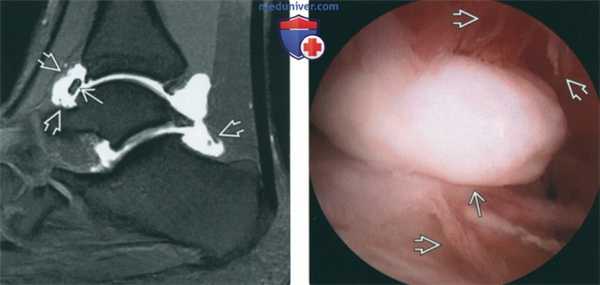

(Слева) МР-артрография в режиме Т1ВИ FS, сагиттальный срез: спереди визуализируется свободное тело. Листовидные выпячивания свидетельствуют о синовите. В этом случае полость голеностопного сустава сообщается с полостью заднего отдела подтаранного сустава, что является вариантом нормы, встречающимся в 15% случаев.

(Справа) Артроскопия голеностопного сустава: в переднем завороте определяются свободное тело и признаки синовита (листовидные выпячивания). Во многих случаях при хронической нестабильности повреждаются костные и мягкотканные структуры как с медиальной, так и с латеральной стороны. Поэтому следует помнить о возможной гиподиагностике вследствие феномена «удовлетворенности поиском».